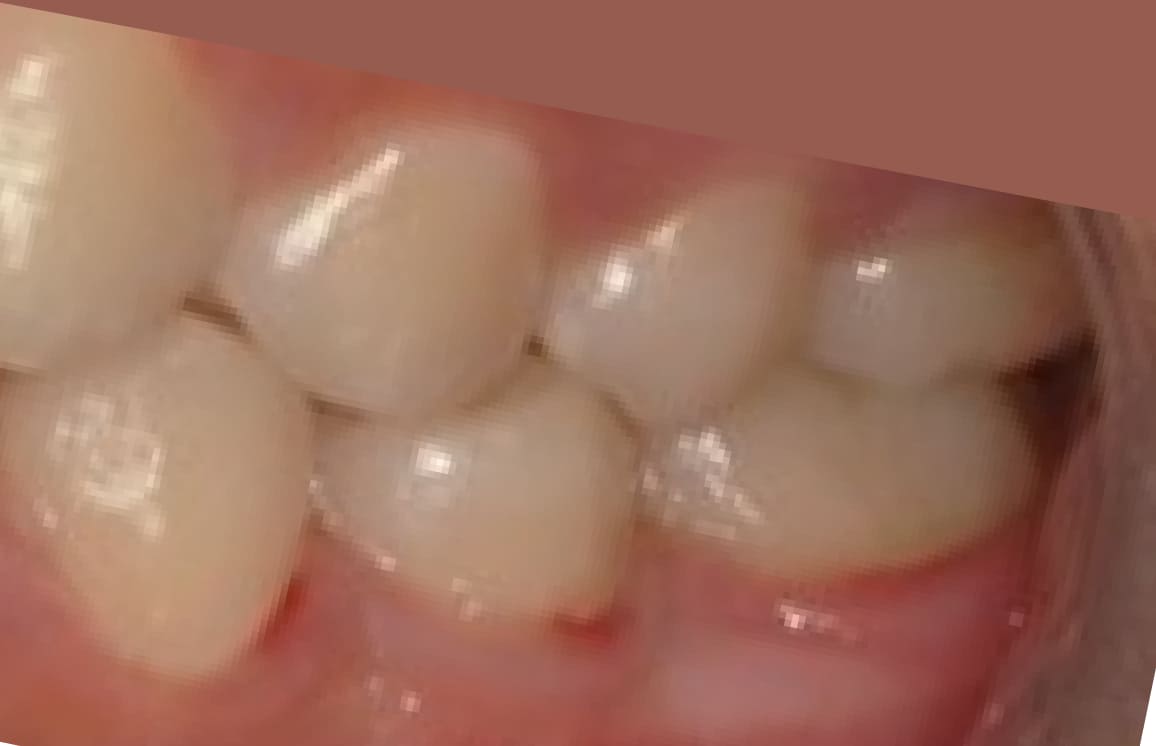

● 歯根が折れ保存不可の歯を抜歯して、そのスペースに八重歯を並べた症例

藤沢デンタルオフィスの虫歯や破折で抜歯後の部分矯正